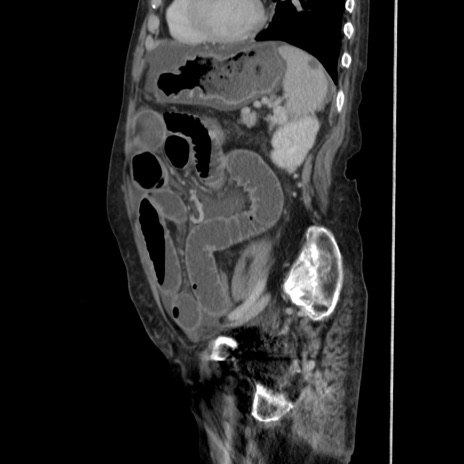

症例31(矢状断像)

【症例】80歳代 女性

【主訴】腹部膨満感

【現病歴】他院にて肝硬変にてフォロー中。1週間前から便秘、腹部膨満感、臍部腫瘤あり受診となる。

【既往歴】肝硬変

【身体所見】腹部膨隆あり、皮膚変化なし、疼痛なし。

【データ】WBC 4600、CRP 0.25